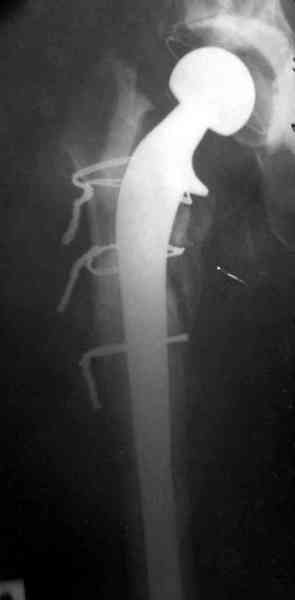

Для спейсера в бедро использовал старый длинный бедренний компонент меньшего диаметра, облепленный со всех сторон цементом с антибиотиком.

Наглухо ушитая рана с дренажом зажила первично, после чего с больной потерял контакт, и только недавно, через 8 лет я осмотрел её. Она без проблем нагружает на конечность и передвигается с помощью трости. От окончательной операции по реконструкции отказывается, довольная результатом.

Имеются литературные данные, когда спейсер держали не более 6 месяцев, но этот случай бьет все рекорды, может быть для наших людей, обременных финансовыми трудностями, нужна другая шкала оценки сроков нахождения спейсеров.

№3-6 снимки с осложнением

и последние снимки.